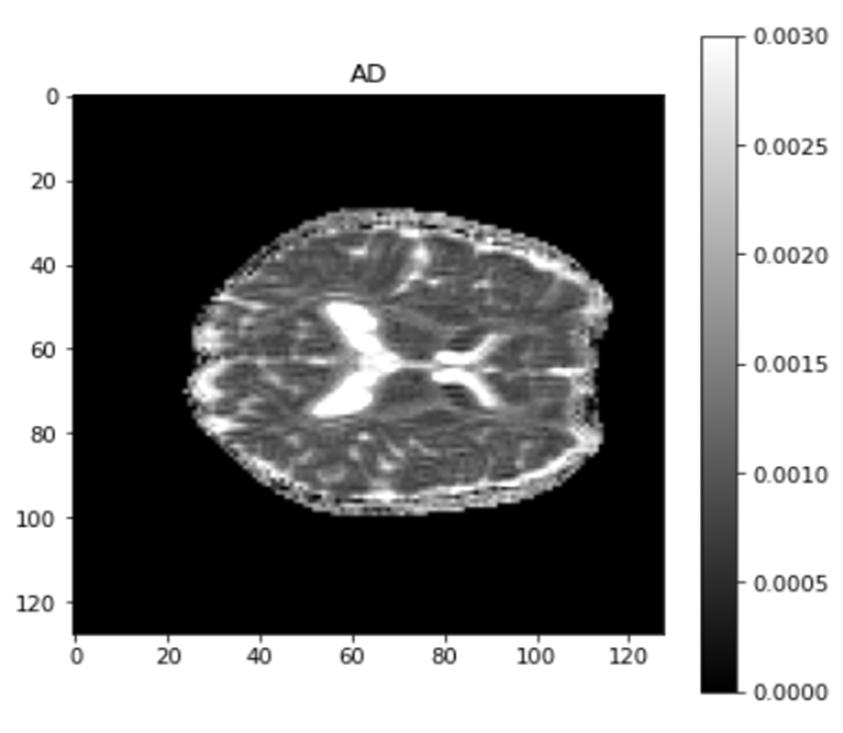

Axial diffusivity (AD) and radial diffusivity (RD) are the Additional measures necessary to further define the tensor if two tensors with different forms provide identical FA values. AD describes the diffusion rate along the primary axis of diffusion, along ( ), or parallel to the axon (and hence, some works refer to it as parallel diffusivity). On the other hand, RD is the average diffusivity along the minor axes(being named perpendicular diffusivity). Where both are measured in mm^2/s.

When it comes to AD and RD maps, we are able to identify changes in the axonal parameter by adjusting the white matter area. This allows us to better understand the connections between neurons. In AD, the main water movement is strongly focused, along primary axis. but in RD, it is focused transverse to the long axis.

Fig. 10 Output AD map